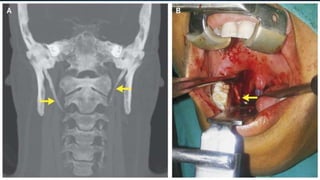

• Final diagnosis :- Based on subjective data & objective data [ CT scan of neck ]

obtained from the patient is assessed to have " Eagle's Syndrome "

• Ct scan of neck :-

1. Mucosal thickening of b/l maxillary sinus with obliterated right osteomeatal

complex

2. Elongated styloid process b/l [ Right – 4.48 cm , Left – 4.41 cm ]

ASSESSMENT • Provisional diagnosis:- Globus hystericus • Final diagnosis :- Based on subjective data & objective data [ CT scan of neck ] obtained from the patient is assessed to have " Eagle's Syndrome "